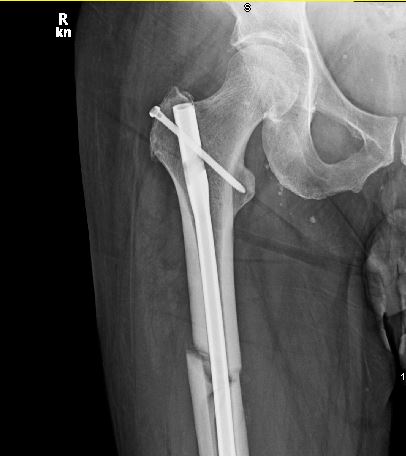

It’s been one year since I broke my femur – you can see the progress of my healing in this image:

I’m 95% healed, back on all my daily activities (including yoga!). The ortho doc said that if I have any trouble doing anything, I should just try harder!

I was in the ER in Santa Fe by 6:00PM – they did surgery ASAP: aligned the bones, drilled out the core, and installed an internal continuous rod, screwed everything together and stapled me up! I was in my room by 3AM.